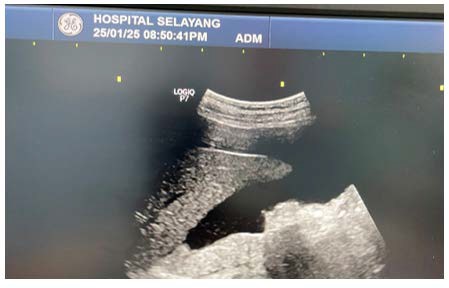

WBCT is increasingly used in trauma settings due to its ability to provide a comprehensive and thorough evaluation of the entire body in a short time frame. It is especially valuable in cases of undifferentiated or cryptogenic shock where initial assessments fail to localize the source of bleeding.

In adrenal trauma, WBCT can detect subtle signs such as adrenal enlargement, hematoma, periadrenal fat stranding, or contrast extravasation. Studies have shown that WBCT improves survival in trauma patients by facilitating early diagnosis and intervention. However, WBCT is often limited by resource constraints, radiation exposure concerns, and clinicians focus on more obvious injuries.

In this case, WBCT was needed in raising suspicion for retroperitoneal bleeding, prompting timely surgical exploration and intervention (Figure 3 and Figure 4).

Figure 3: WBCT Shows Periadrenal Streakiness Appearance

Figure 4: WBCT Shows Contrast Extravasation